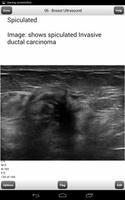

이것은 초음파 유방 플래시 카드 프로그램의 라이트 버전입니다. 정식 버전에는 ARDMS 모유 보드를 공부하고 통과시키는 데 도움이되는 1084 개의 플래시 카드가 포함되어 있습니다.